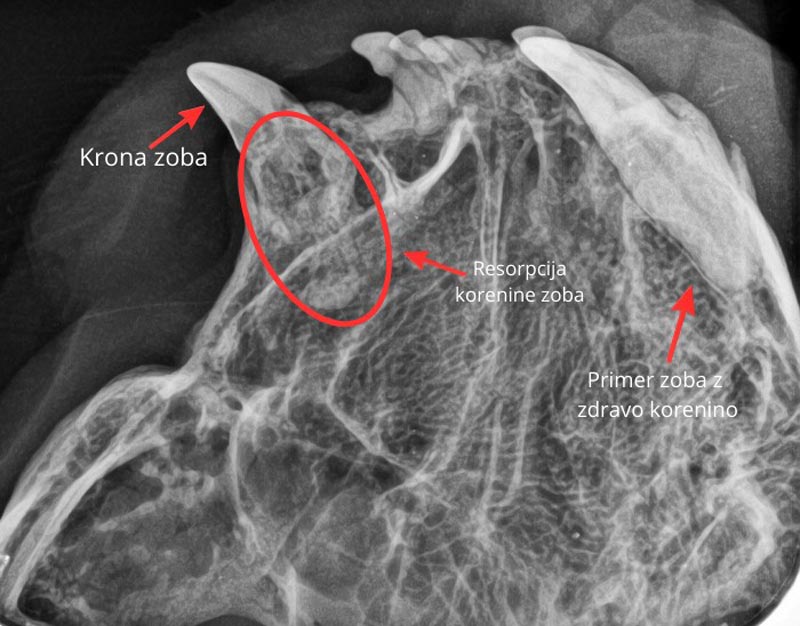

Del zoba, ki ga vidimo v gobcu, se imenuje krona. Predstavlja del zoba, med tem ko je preostanek skrit in ni viden. Zobje se razlikujejo po velikosti, obliki in številu korenin. Kljub temu imajo nekaj skupnega. Zob lahko navzven deluje zdrav, v notranjosti pa je lahko poškodovan ali vnet.

Če takšnega zoba ne zdravimo, lahko žival občuti nelagodje in bolečino. Težave se lahko stopnjujejo. S prostim očesom ne moremo oceniti celotnega stanja zoba. Zato je nujna uporaba zobnega rentgena (zobni RTG). Ta omogoča slikanje vsakega zoba posebej.

Na podlagi slike dobimo celosten vpogled v stanje zoba. Tako določimo naslednji korak. Če se odločimo za ekstrakcijo, po puljenju ponovno uporabimo zobni RTG. Tako preverimo, ali je korenina v celoti odstranjena.

Pri poškodovanih koreninah se pogosto zgodi, da se med ekstrakcijo zdrobijo. To s prostim očesom pogosto ni vidno. Če ostanki ostanejo v dlesni, lahko povzročijo nove zaplete. Med njimi so kronična vnetja, trajna bolečina in nastanek fistul.

Sodobne smernice poudarjajo, da je zobni RTG pri stomatološkem posegu nujen. Veterinarji se pogosto srečujemo z željami lastnikov, ki želijo hitro puljenje majavega zoba. Toda tak pristop je zastarel. Pregled z zobnim RTG je minimalni strokovni standard. Ekstrakcije brez zobnega RTG-na ga ne dosegajo več.